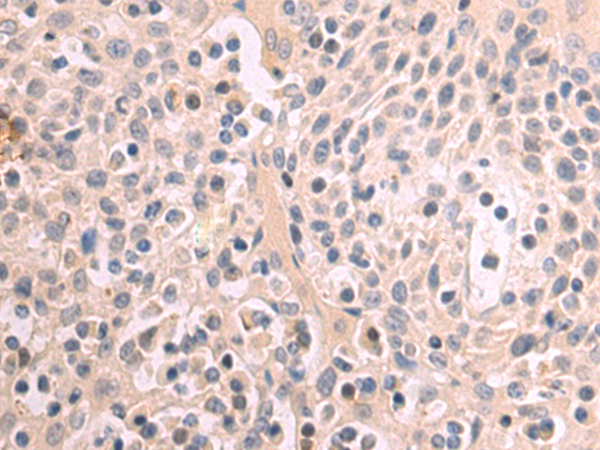

分类: 科研抗体货号: P01722别名: 1R20; BL34; IER1; IR20; HEL-S-87应用: WB,IHC反应种属: Human, Mouse